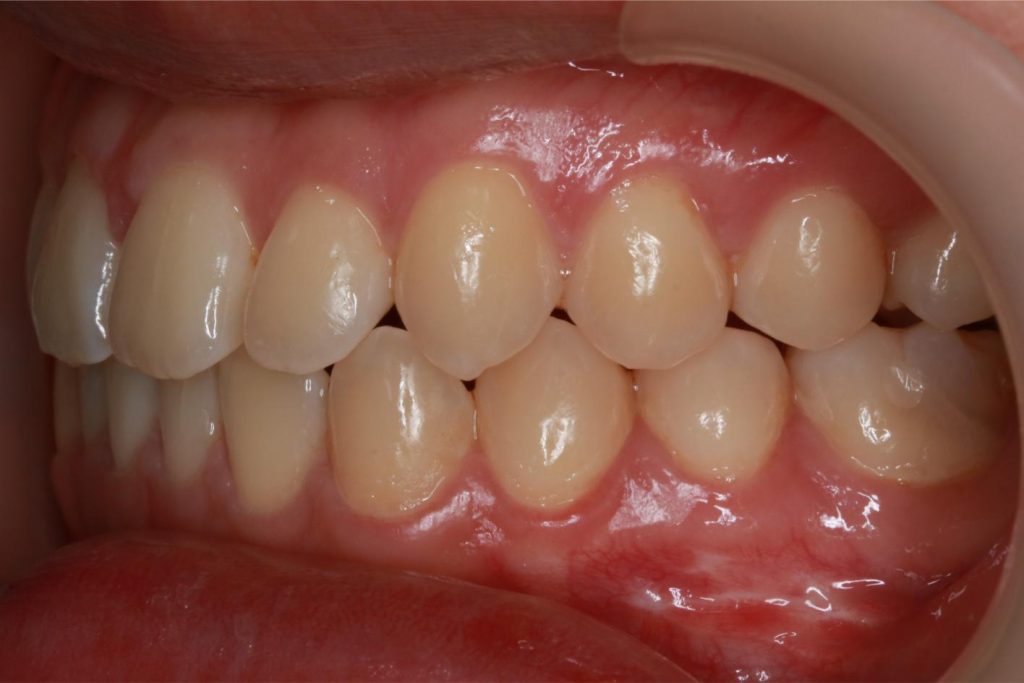

Before and After Images